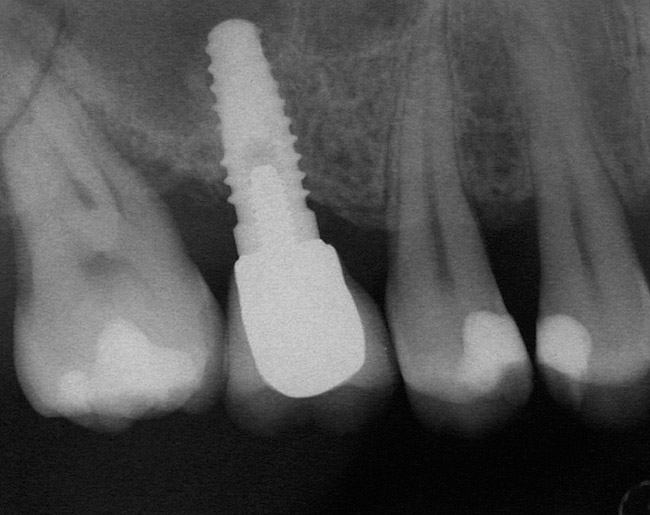

A 53-year-old female was referred for evaluation of a fracture of tooth No. 24. The tooth had been treated endodontically 5 years prior. The radiograph revealed a complete fracture of the tooth involving the crown (Figure 12). Tooth extraction and immediate placement of a an implant that was 10 mm in length and 3.75 in diameter was planned.

At the time of surgery, the tooth was extracted without harvesting any mucosal flap because the implant site was prepared by means of a pilot drill bur (Figure 13) and alternating osteotomes (Figure 14A and Figure 14B). The implant was positioned and showed primary stability. The implant was loaded 2 days after surgery. Then, splinted PFM crowns supported by custom gold abutments were delivered. At 6 months posttreatment, the radiograph revealed no bone resorption and the clinical result was optimal (Figure 15A and Figure 15B).

Figure 12  Preoperative radiograph shows fractured tooth No. 24.

Figure 15B Posttreatment radiograph, 6 months after the initial surgery.

Figure 15  Posttreatment radiograph, 6 months after the initial surgery.

Figure 15b